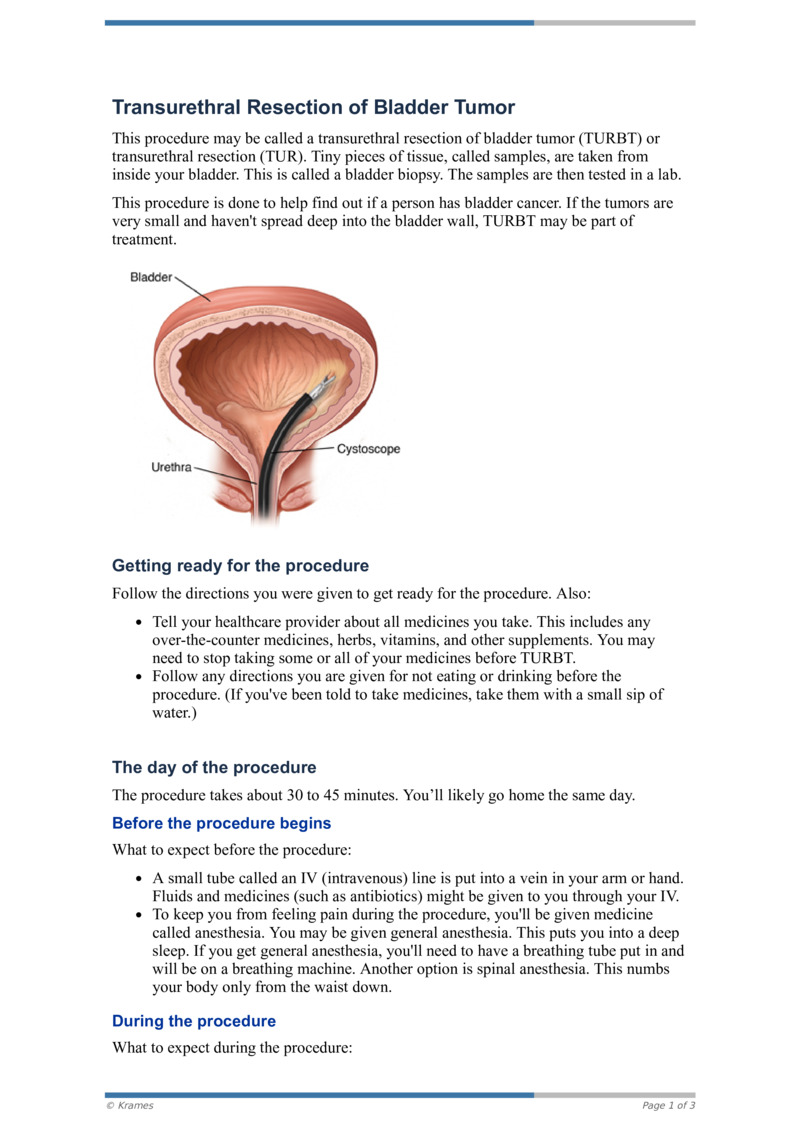

PDF Transurethral Resection Of Bladder Tumor HealthClips Online

https://twnlivestorage1.blob.core.windows.net/twn-media-public/KRM62461A/KRM62461A_en_g00.jpg

PDF Transurethral Resection Of Bladder Tumor HealthClips Online